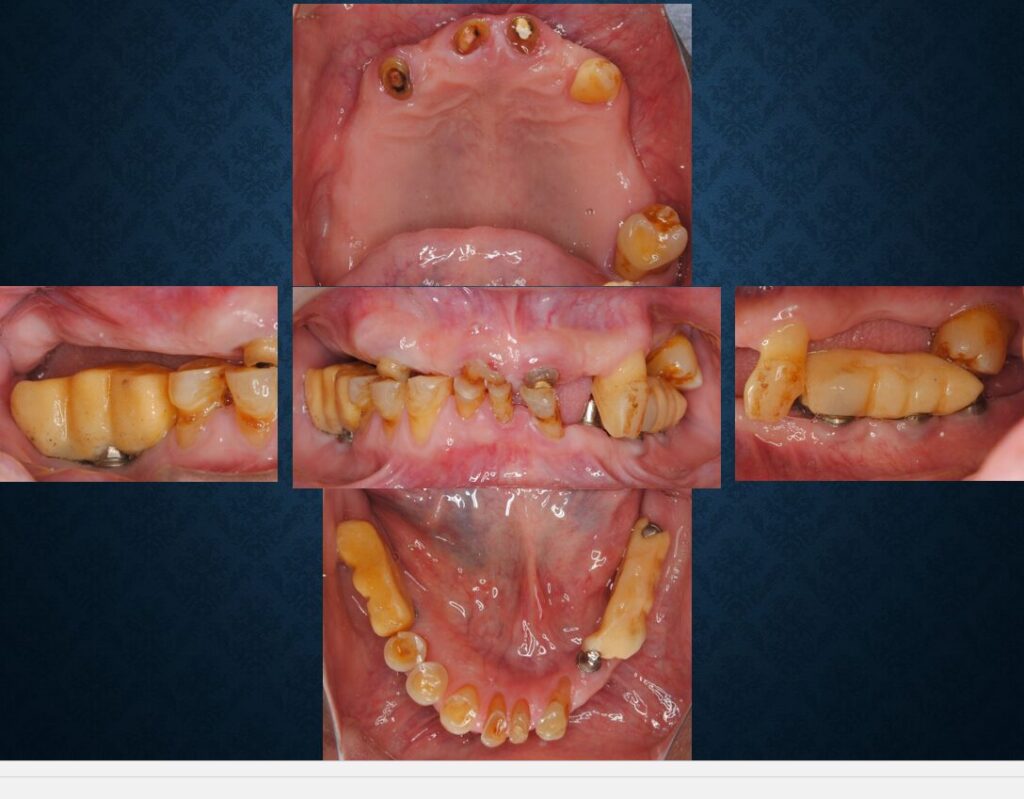

TさんはF銀行の方で60代男性でした。「他院でインプラントを入れたが乱暴なのでこちらで診て欲しい」「上もインプラントでやって欲しい」そのとの事で来院されました。お口の中はこんな状況でした。

レントゲンを撮ってみると様々な問題点が浮き彫りになりました。

お口の中を型取りして石膏をついで模型を作ってみると、今後治療を引き継いでいく上で頭を抱えたくなるような問題点が山積していました。インプラントが入っている位置や方向が困った事になっていました。